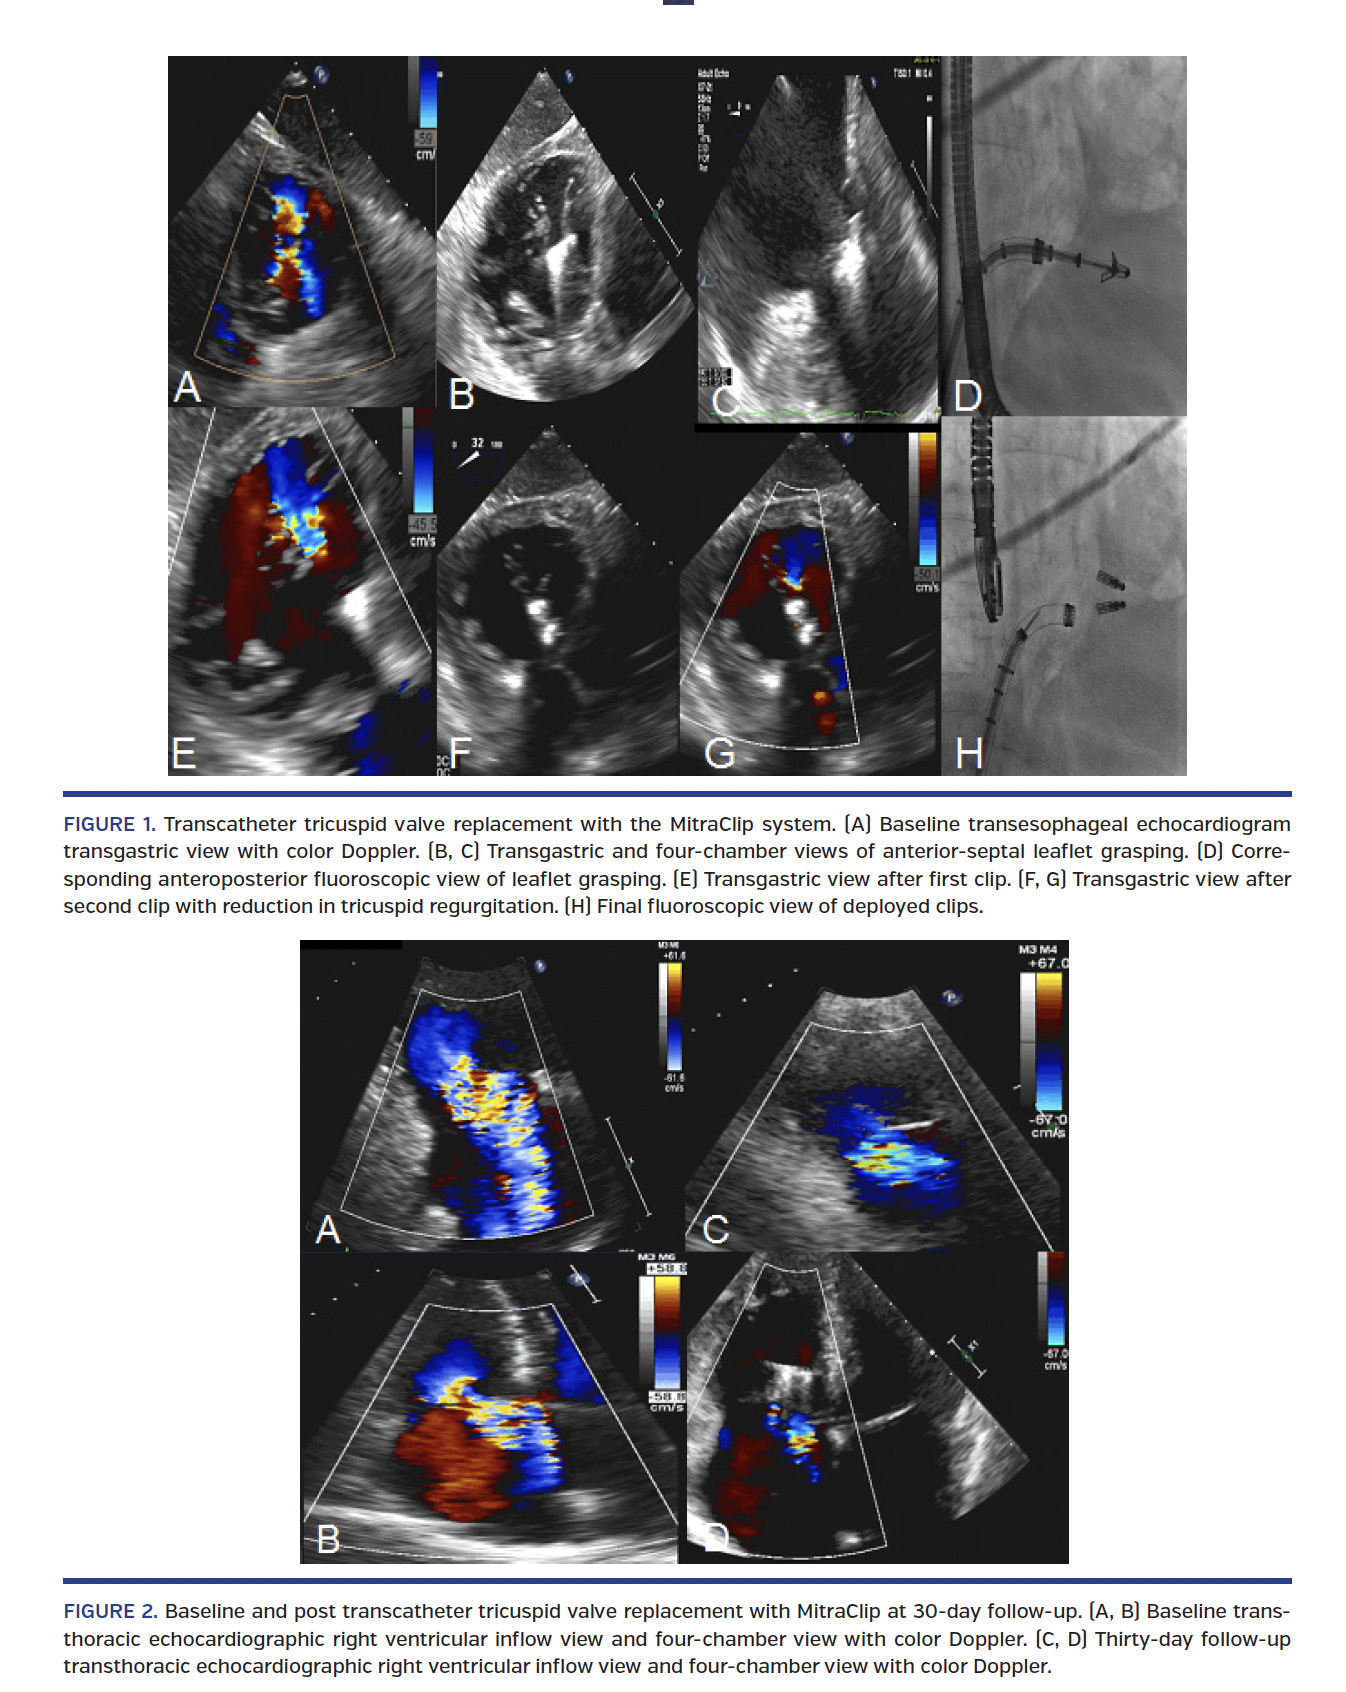

The initial strategy was to target the posterior leaflet flail segment. The posterior and anterior leaflets were successfully grasped at their tips, but this did not impact TR severity and so were released. The posterior and septal leaflets could not be grasped due to the posterior leaflet perforation. Subsequently, we targeted the anterior and septal leaflets. The first clip was placed at the base of the leaflets, while the second clip was placed close to the leaflet tips, with an acute reduction in TR by one grade (Figure 1, Video 1). The patient remained stable and was discharged 2 days later. At 30-day follow-up, the patient reported functional improvement to New York Heart Association class II, with 5 kg weight loss and less peripheral edema. Transthoracic echocardiography demonstrated reduction of TR into the moderate range (Figure 2), with right ventricular reverse remodeling and increased left ventricular stroke volume.